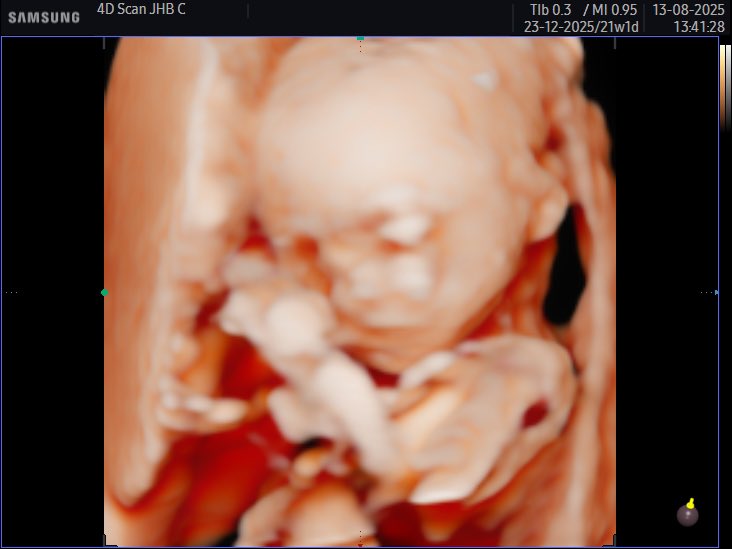

Super surreal 🥺🥰 the way this little girl kicks already, she might be a little athlete but the mouse will be going in her hand if I can help it 🤭

Little bean 🫘 due 23rd December ✨ got lucky and baby woke up during the sonar and wiggled around for us

Cjay tweet mediaCjay tweet mediaCjay tweet media